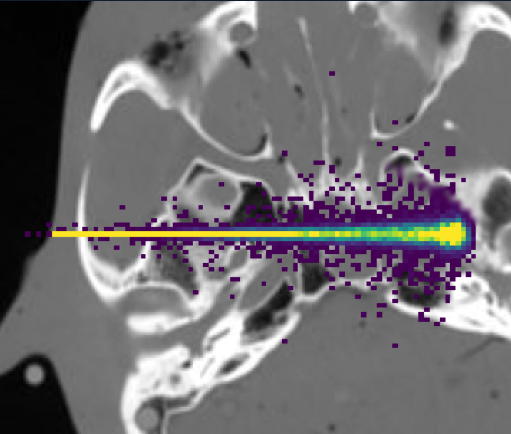

This project is a collaborative study between LPSC in Grenoble, the Centre Antoine Lacassagne in Nice and the research team imXgam at CPPM to develop Prompt Gamma Time Imaging (PGTI) for range monitoring in hadrontherapy. This work is supported by the ERC starting grant PGTI of Sara Marcatili (LPSC).

M. Jacquet et al., A time-of-flight-based reconstruction for real-time prompt-gamma imaging in protontherapy, Phys. Med. Biol. 66 (2021) 135003